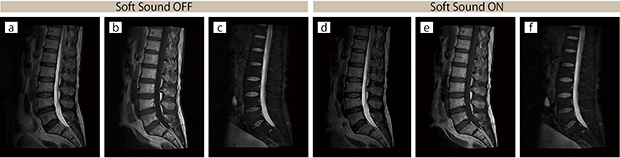

■臨床例2:腰椎

腰椎撮像におけるSoft Sound OFF(a〜c)/ON(d〜f)の比較。

スライス厚はすべて4mm。撮像時間はほぼ同等となっている。

a:T2 WI,SAG,2:46

b:T1 WI,SAG,2:42

c:T2 WI,Fatsat,SAG,2:43

d:T2 WI,SAG,2:51

e:T1 WI,SAG,2:46

f :T2 WI,Fatsat,SAG,2:52